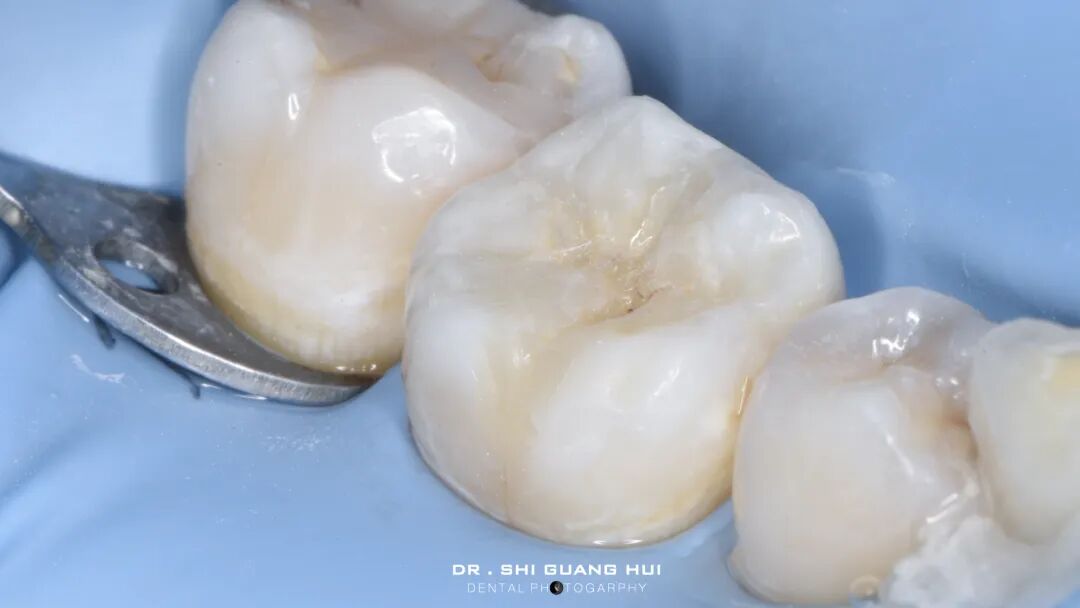

局部麻醉下进行去除腐质,可见远中邻面边缘位于龈下。由于近髓,剩余核心区域腐质橡皮障隔离后再进行去除。

橡皮障隔离患牙,去净腐质,然后进行详细的生物力学分析,远中舌尖无牙本质支撑,需要牙尖覆盖,降低1.5mm左右,远中颊尖厚度足够。近中邻面边缘嵴完整,远中邻面边缘需要进行CMR。

圈型成型片完美隔离,喷砂牙本质表面,将牙本质表面进行37%磷酸酸蚀15秒,轻轻风干5秒后涂布粘接系统,进行IDS。

进行IDS,远中邻面进行CMR